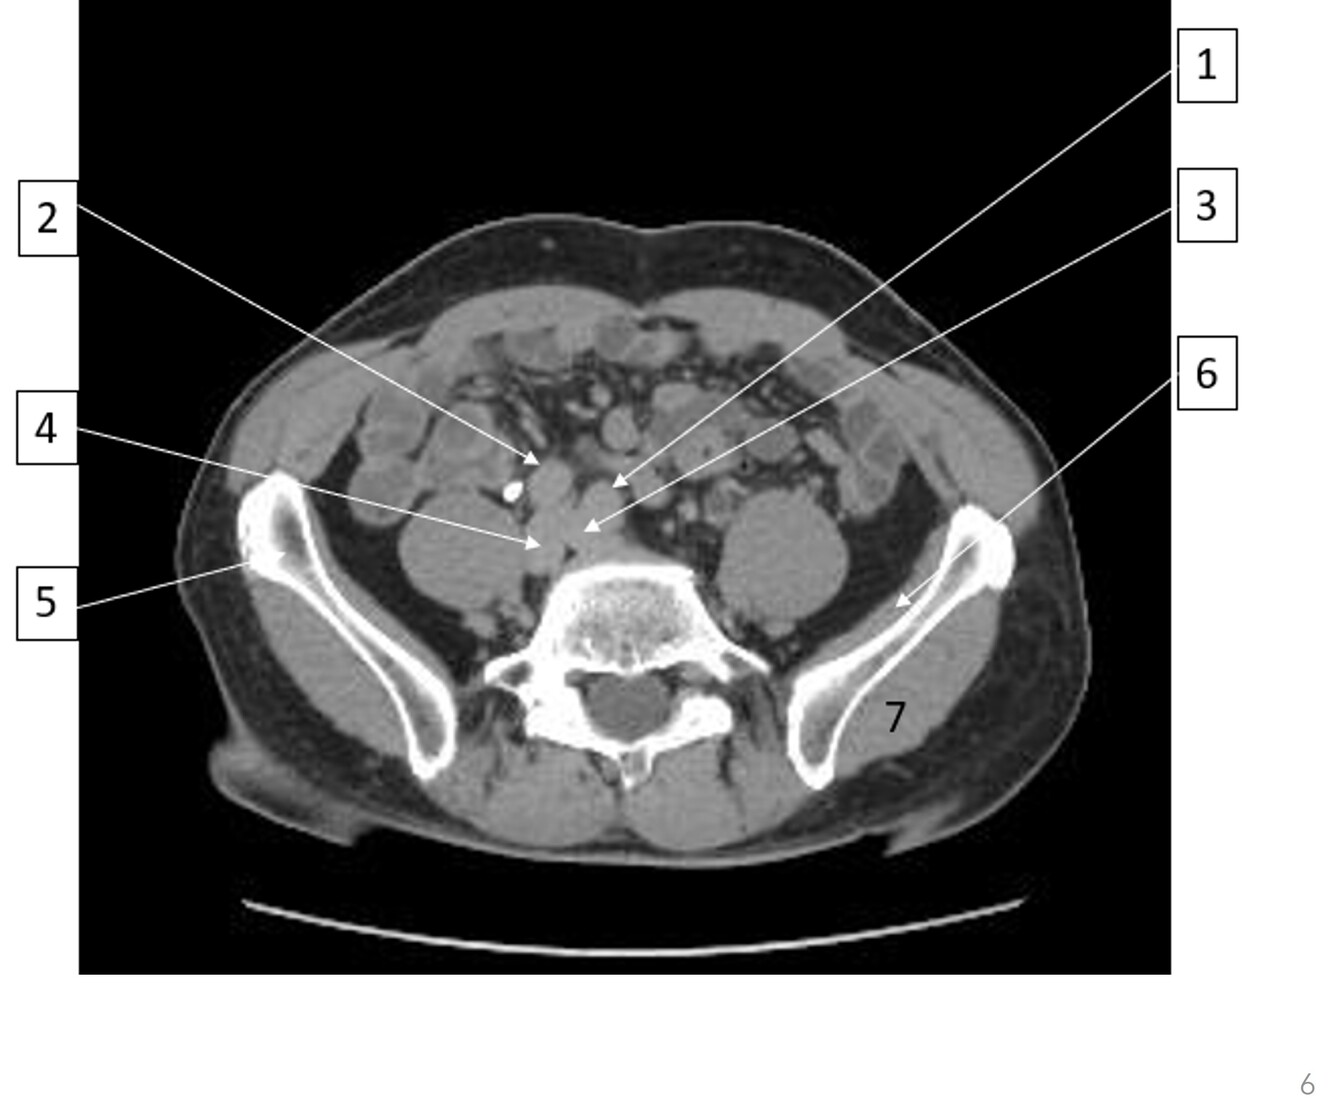

10

Q

Label 6-9

A

6-Convergence of lt external and internal iliac veins

7-Bifurcation of rt common iliac artery

8-Lt external oblique

9-Lt gluteus medius

11

Label 1-6

1. Lt iliopsoas

2. Rt external iliac artery

3. Rt external iliac vein

4. Lt internal iliac artery

5. Lt internal iliac vein

6. Rt gluteus minimus